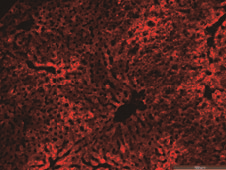

和元生物AAV感染结果

和元生物AAV-PAN感染结果

和元AAV-LUNG感染肺部结果

AAV感染脂肪